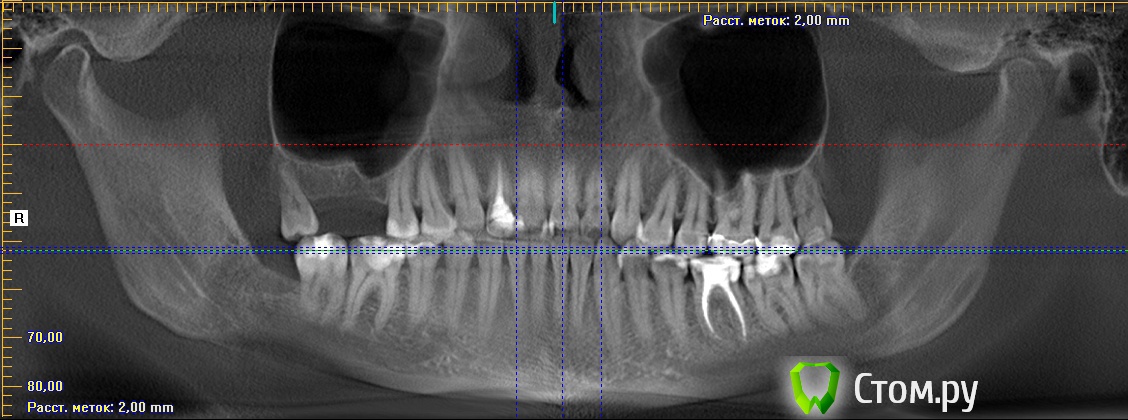

Майло Опубликовано 18 марта, 2014 Автор Поделиться Опубликовано 18 марта, 2014 (изменено) Здравствуйте, наконец сделала кт. Сегодня появилась небольшая боль над правой бровью (после лазера прошла, к вечеру появилась опять). Насморк и заложенность присутствуют. Еще сегодня опять поговорила со своим хирургом имплантологом. По симптомам сказал, что похоже присоединилась какая-то лор болячка и наверное надо сходить к лору. По кт сказал, что все нормально. Немного сужена пазуха справа, но учитывая, что я аллергичная, это нормально. Про капли типа Полидекса, сказал спросить у лора. Завтра я делаю последний лазер, по прежнему промываю нос Отривином Бэби (мне так удобней), пью кларитин, "выбиваю" нос по необходимости, но стараюсь пореже (2-3 раза в день). Еще он отдал кт через 2 недели после имплантации, на всякий случай прикреплю и этот снимок. Самый первый снимок кт был сделан через 2 недели после имплантации. Второй и третий сегодня. Подскажите, я так понимаю данное кт не показывает есть ли у меня гайморит? (к лору смогла записаться аж на 26-е) И все равно хотелось бы узнать ваше мнение по поводу состояния имплантов, есть ли там воспаление или "нагноение"? Изменено 18 марта, 2014 пользователем Майло Ссылка на комментарий

Майло Опубликовано 18 марта, 2014 Автор Поделиться Опубликовано 18 марта, 2014 (изменено) Решила еще добавить пару кадров своих пазух, вначале показалось что справа что-то есть (рис1), потом поняла это костный материал и импланты (рис2). Надеюсь так должно быть. И еще вопрос, может и "тупой", такое яркое свечение имплантов, особенно заметно на фото в профиль, это нормально? Изменено 18 марта, 2014 пользователем Майло Ссылка на комментарий

Bier Опубликовано 18 марта, 2014 Поделиться Опубликовано 18 марта, 2014 выглядит все неплохо, и пазуха чистая. Гайморита у вас нет. Сходите к ЛОРУ 2 Ссылка на комментарий

Майло Опубликовано 25 марта, 2014 Автор Поделиться Опубликовано 25 марта, 2014 (изменено) Здравствуйте, не могла ждать хорошего лора до 26го и отправилась к другому (надеюсь, не менеее хорошему) в другую клинику. Врач не стал смотреть снимок, под странным предлогом, что смотрит снимки сделанные только у них в клинике, предложил сделать через неделю при повторном посещении. Но не суть. На основании осмотра и моих рассказов и симптомов, мне назначили Полидэкс капли, АЦЦ лонг и Эриус. Ацц выпила только 2 раза, так как заболел желудок от него сильно. С Полидэксом стало дышать лучше, но вот сегодня на четвертый день лечения стали болеть глаза и если вчера боль была только к вечеру, то сегодня и утром, особенно беспокоит глаз справа, где была операция и еще там же над бровью(( А еще сегодня утром заметила много засохших выделения из глаз. Не знаю может это от Полидэкса? Контрольный осмотр у лора у меня в пятницу аж. Да, температура у меня упала, сегодня вообще странно в 11 дня была 36,3, наверное реакция на гормон который входит в состав. А вообще состояние то холодно, то прям жарко, мне всего 30 лет, поэтому думаю это связано именно с зубами или носом, не знаю, слабость и потливость.. Врач ничего не сказал по поводу боли в зубе который находится на другой челюсти верхняя левая шестерка или семерка, пока точно не поняла, но скорее всего шестерка. Странно, но после первых 2-х закапыванией полидекса сразу ощутила облегчение, зуб конечно бывает постреливает и при надкусывании бывает боль, но не так как раньше. Тоже списываю на действие гормона, так как где то читала, что при сильных болях иногда используют минимальные дозы гормонов (может я ошибаюсь, не судите строго). Хотелось бы услышать ваше мнение по прикрепленным снимкам, есть ли наличие воспаления в 6м или 7м зубе? Как еще это можно проверить если не по снимкам. Когда зуб начал беспокоить подходила к стоматологу, она постучала, полила холодной водой, у меня пару раз стрельнуло, но она сказала возможно из-за смены пасты или эксплуатации этого зубного ряда или лор заболевания и если разболится прийти. А также, как вы считаете, не слабоватое ли лечение мне прописал доктор??, учитывая, что стоят импланты, оч боюсь образования свища или хронического гайморита, опять же не понятного происхождения, то ли аллергического (так как после операции и синус-лифтинга, пока не стала принимать антигистамины и гормоны в нос облегчения не было, все чисалось) или все-таки бактериального (от зуба с другой стороны или по другим причинам)). Да еще забыла добавить, лор сказал, что такое кт не информативное, так как не все видны пазухи, видимо имелись ввиду верхние(( Изменено 25 марта, 2014 пользователем Майло Ссылка на комментарий

Bier Опубликовано 14 апреля, 2014 Поделиться Опубликовано 14 апреля, 2014 Покажите пазухи на кт свежем еще раз, в предыдущем сообщении вы другую пазуху показали, с зубами Ссылка на комментарий

Bier Опубликовано 14 апреля, 2014 Поделиться Опубликовано 14 апреля, 2014 Странно, у вас абсолютно чистая пазуха. Если у Вас есть фейсбук, могу вас сконтачить с более толковым ЛОРом Просто "зеленые сопли" о которых вы говорите должны где-то быть. Ссылка на комментарий